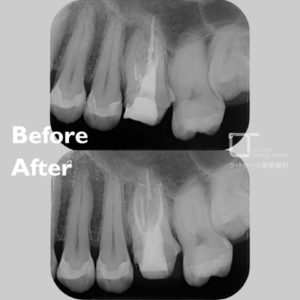

精密根管治療・20代(女性)|「以前治療した歯に鋭い痛みと鈍い痛みを感じる」

治療方法 精密根管治療 施術費用 ¥143,000 通院回数 1回 通院期間 メリット 感染した神経や組織を除去して痛みの原因を取り除き、ご自身の天然歯を残せる可能性を高めます。周囲組織への悪影響を抑えることが期待できます。 リスクと副作用 精密根管治療は保険適用外です。精密根管治療後には痛みや違和感が続くことがあり、歯が脆く割れやすくなる場合があります。感染が除去できなかった場合は再発のリスクがあります。 精密根管治療の治療例です。「以前、虫歯の治療をした歯が痛い。鋭い痛みと鈍い痛みを感じる時がある。」とのことで来院されました。当院にて診査・診断を行い […]